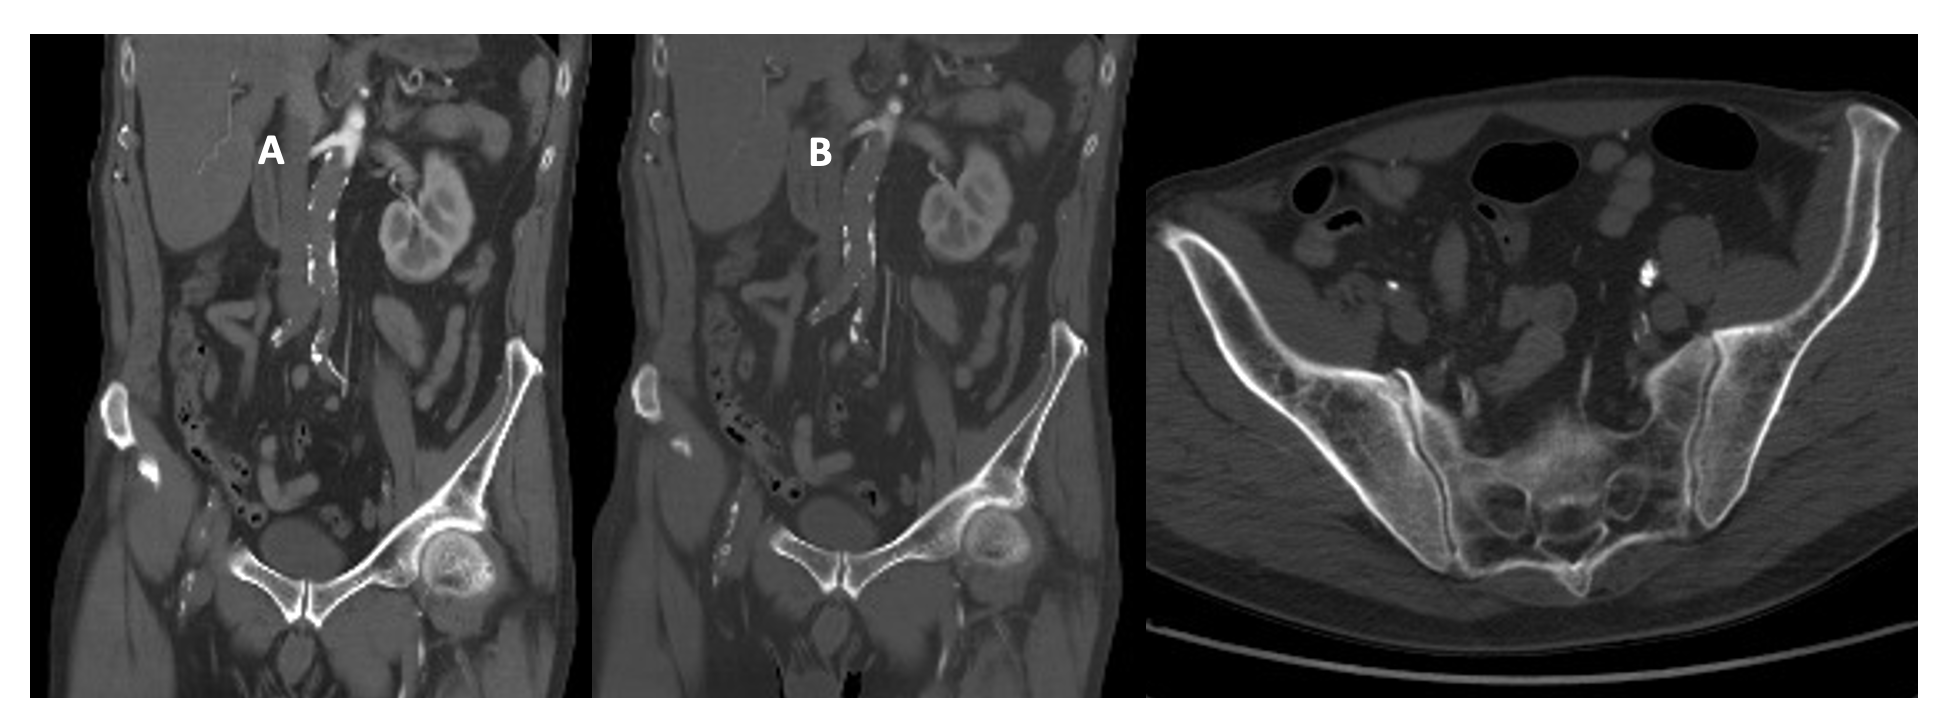

The patient was transferred to the hospital ward and discharged on the 8th postoperative day with closed fasciotomies and preserved bilateral pedal pulses. During the hospitalization, a follow-up CT scan for his bilateral pneumonia showed a patent endograft without leaks (Figure 2). Two months later, the patient received treatment for his vocal cord carcinoma from the otolaryngology department through radiotherapy. In the most recent outpatient follow-up 1 year ago, he maintained distal pulses, and ultrasound evaluation showed the endograft without leaks and patent femorofemoral bypass.